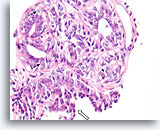

Papilloom, Borst FNA, Celblok.

Deze afbeelding van dezelfde FNA als in afbeelding 18 bevat een duidelijk papillaire architectuur.

10X

Papilloom, Borst FNA, Celblok.

Deze afbeelding van dezelfde FNA als in afbeelding 18 bevat een duidelijk papillaire architectuur.

10X

Papilloom, Borst FNA, Celblok.

Met een sterkere vergroting kan een gemengde celpopulatie gezien worden die het oppervlak en de onderliggende melkgangen bekleden. Een rij myoepitheliale cellen is zichtbaar tussen de ductale cellen en het onderliggende stroma (pijl). Let op de spleetachtige ruimte die kenmerkend is voor typische hyperplasie (open pijl).

40X

Papilloom, Borst FNA, Celblok.

Met een sterkere vergroting kan een gemengde celpopulatie gezien worden die het oppervlak en de onderliggende melkgangen bekleden. Een rij myoepitheliale cellen is zichtbaar tussen de ductale cellen en het onderliggende stroma (pijl). Let op de spleetachtige ruimte die kenmerkend is voor typische hyperplasie (open pijl).

40X

Papilloom, Borst FNA, Celblok.

Let op de bijmenging van bleke myoepitheliale cellen (pijlen) en de rijping van de ductale cellen wanneer zij zich verder van het basaalmembraan stratificeren (open pijl).

40X

Papilloom, Borst FNA, Celblok.

Let op de bijmenging van bleke myoepitheliale cellen (pijlen) en de rijping van de ductale cellen wanneer zij zich verder van het basaalmembraan stratificeren (open pijl).

40X

Papilloom, Borst FNA, Celblok.

Door histologische coupes te maken, kunnen de samenstelling, architectuur en cytologische kenmerken van de grotere papillaire fragmenten bestudeerd worden. Myoepitheliale cellen zijn duidelijk aanwezig (pijlen) en en wordt geen stratificatie van de ductale cellen waargenomen.

60X

Papilloom, Borst FNA, Celblok.

Door histologische coupes te maken, kunnen de samenstelling, architectuur en cytologische kenmerken van de grotere papillaire fragmenten bestudeerd worden. Myoepitheliale cellen zijn duidelijk aanwezig (pijlen) en en wordt geen stratificatie van de ductale cellen waargenomen.

60X